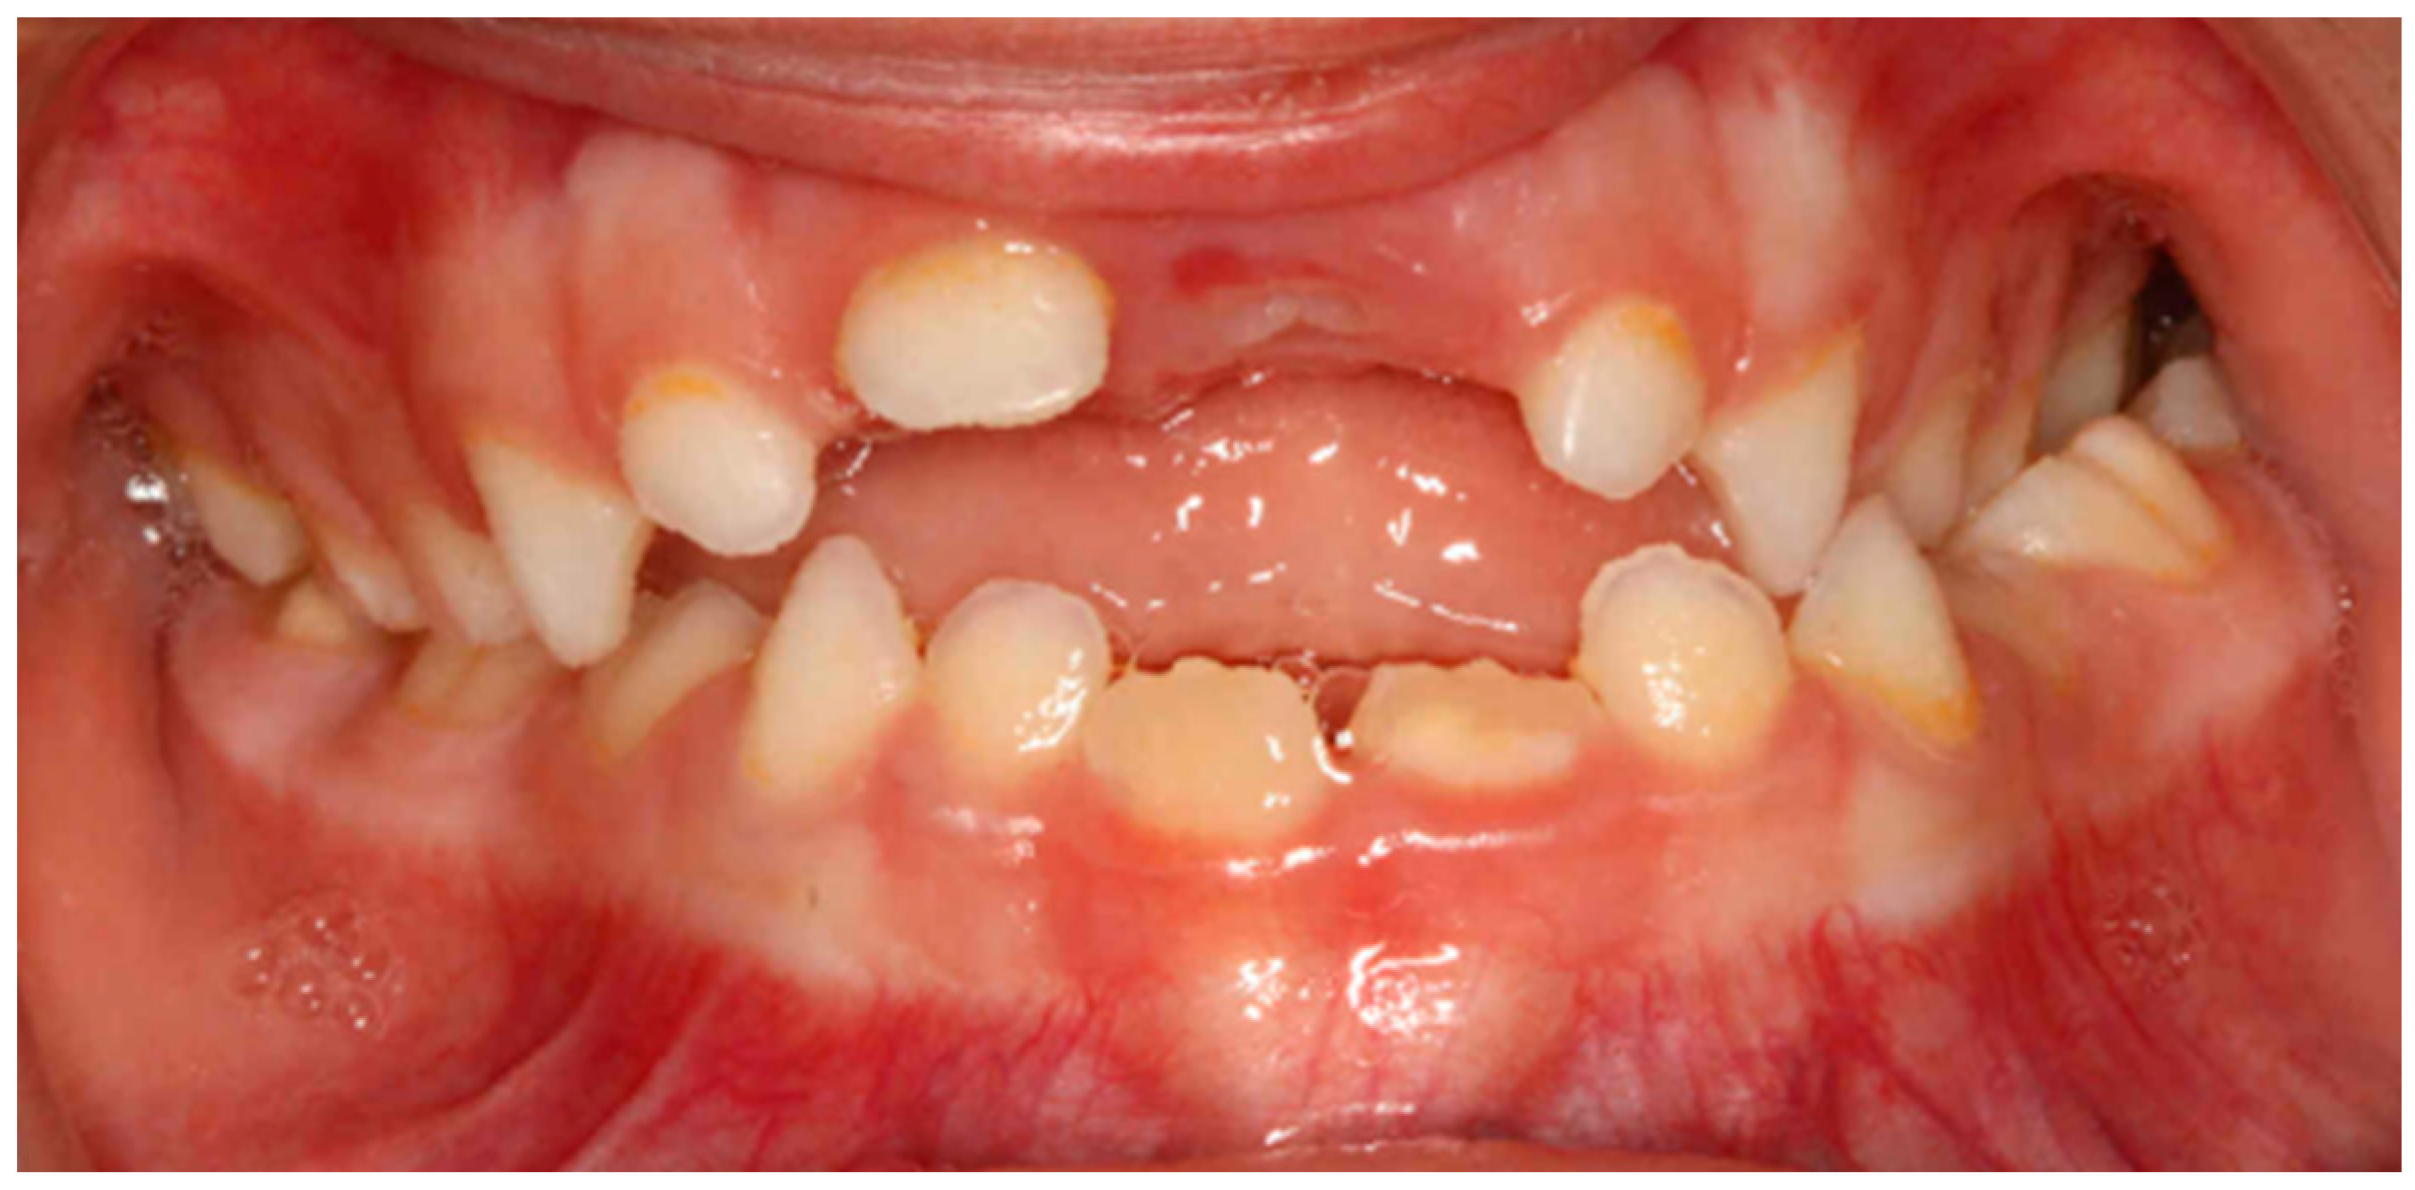

In the horizontal plane, a statistically significant relationship was found between oral respiration and unilateral posterior crossbite (p < 0.05) with a very strong relationship (V > 0.5) (Figure 3). Similarly, a unilateral posterior crossbite also had a statistically significant relationship with immature swallowing (p < 0.05) and with the persistence of the pacifier for more than 2 years (p < 0.05) (Table 4).

Figure 3.

Intraoral photograph of an anterior open bite and unilateral posterior crossbite due to pacifier use for more than 2 years.